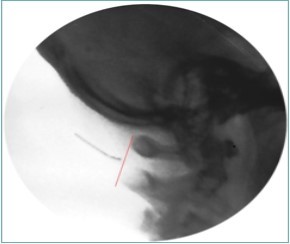

Because of the proximity to the vertebral artery and the potential risk of intravascular injection, few interventionalists have been interested in AA injections, and, since the proximal GON travels over the posterior arch of the atlas, even fewer have been interested in direct injections of the proximal GON. In an effort to avoid the “locked-in” syndrome complication seen with occipital injections, Dr. Gabor Racz developed a suboccipital approach to the suboccipital space in 1982, which has recently become more popular7, 8. A curved, bullet-tipped needle with side port injection, attached tubing, and wings (dubbed the “Stealth needle”™ because of its resemblance to the Stealth bomber) Figure 5 is used to approach the suboccipital triangle from above. Since the underlying pathology is usually bilateral, the procedure is usually performed bilaterally.The patient is positioned prone on the fluoroscopy table, with the neck in flexion; the hair is pulled cephalad, and the suboccipital area is sterilely prepped and draped. The inion and conjoined tendon are identified by palpation and the nuchal line is identified by fluoroscopy; the entry site should be 2cm lateral to the midline on the nuchal ridge. After making sure by palpation that the planned entry is not directly over the occipital artery, a small skin wheal of local anesthetic is injected via a 30g needle. Because the galea is so strong, an 18g needle is used to create a small stab incision in the scalp and deep fascia to facilitate the entry of the blunt-tipped needle. Standing at the head of the bed, the Stealth needle is held by the wings like a butterfly IV needle, and, with tip facing down and toward the feet Figure 6 the needle is advanced caudally. The needle position is initially identified on an anterior-posterior fluoroscopy view, with the target medial to the superior pars of C2 Figure 7 The needle is advanced through the muscle and fascial layers of the trapezius and semispinatus with confirmation of location on lateral view, aiming for the superior lamina of C2 at the level of the spinous processes Figure 8. Contrast is injected to verify needle placement Figure 9 followed by 10 cc of local anesthetics and steroids (4.5ccs 0.2% ropivicaine, 4.5ccs 1% lidocaine, and 10mg of dexamethasone on each side) to perform an adhesiolysis, freeing up the greater occipital nerves Figure 10 Because this technique is usually performed bilaterally, lower concentrations of local anesthetic are used to avoid toxicity issues.

Figure 8.Lateral fluoroscopic image showing the needle in the suboccipital space; red shows the level of the spinous processes (red line). Image Courtesy of Gabor Racz, MD